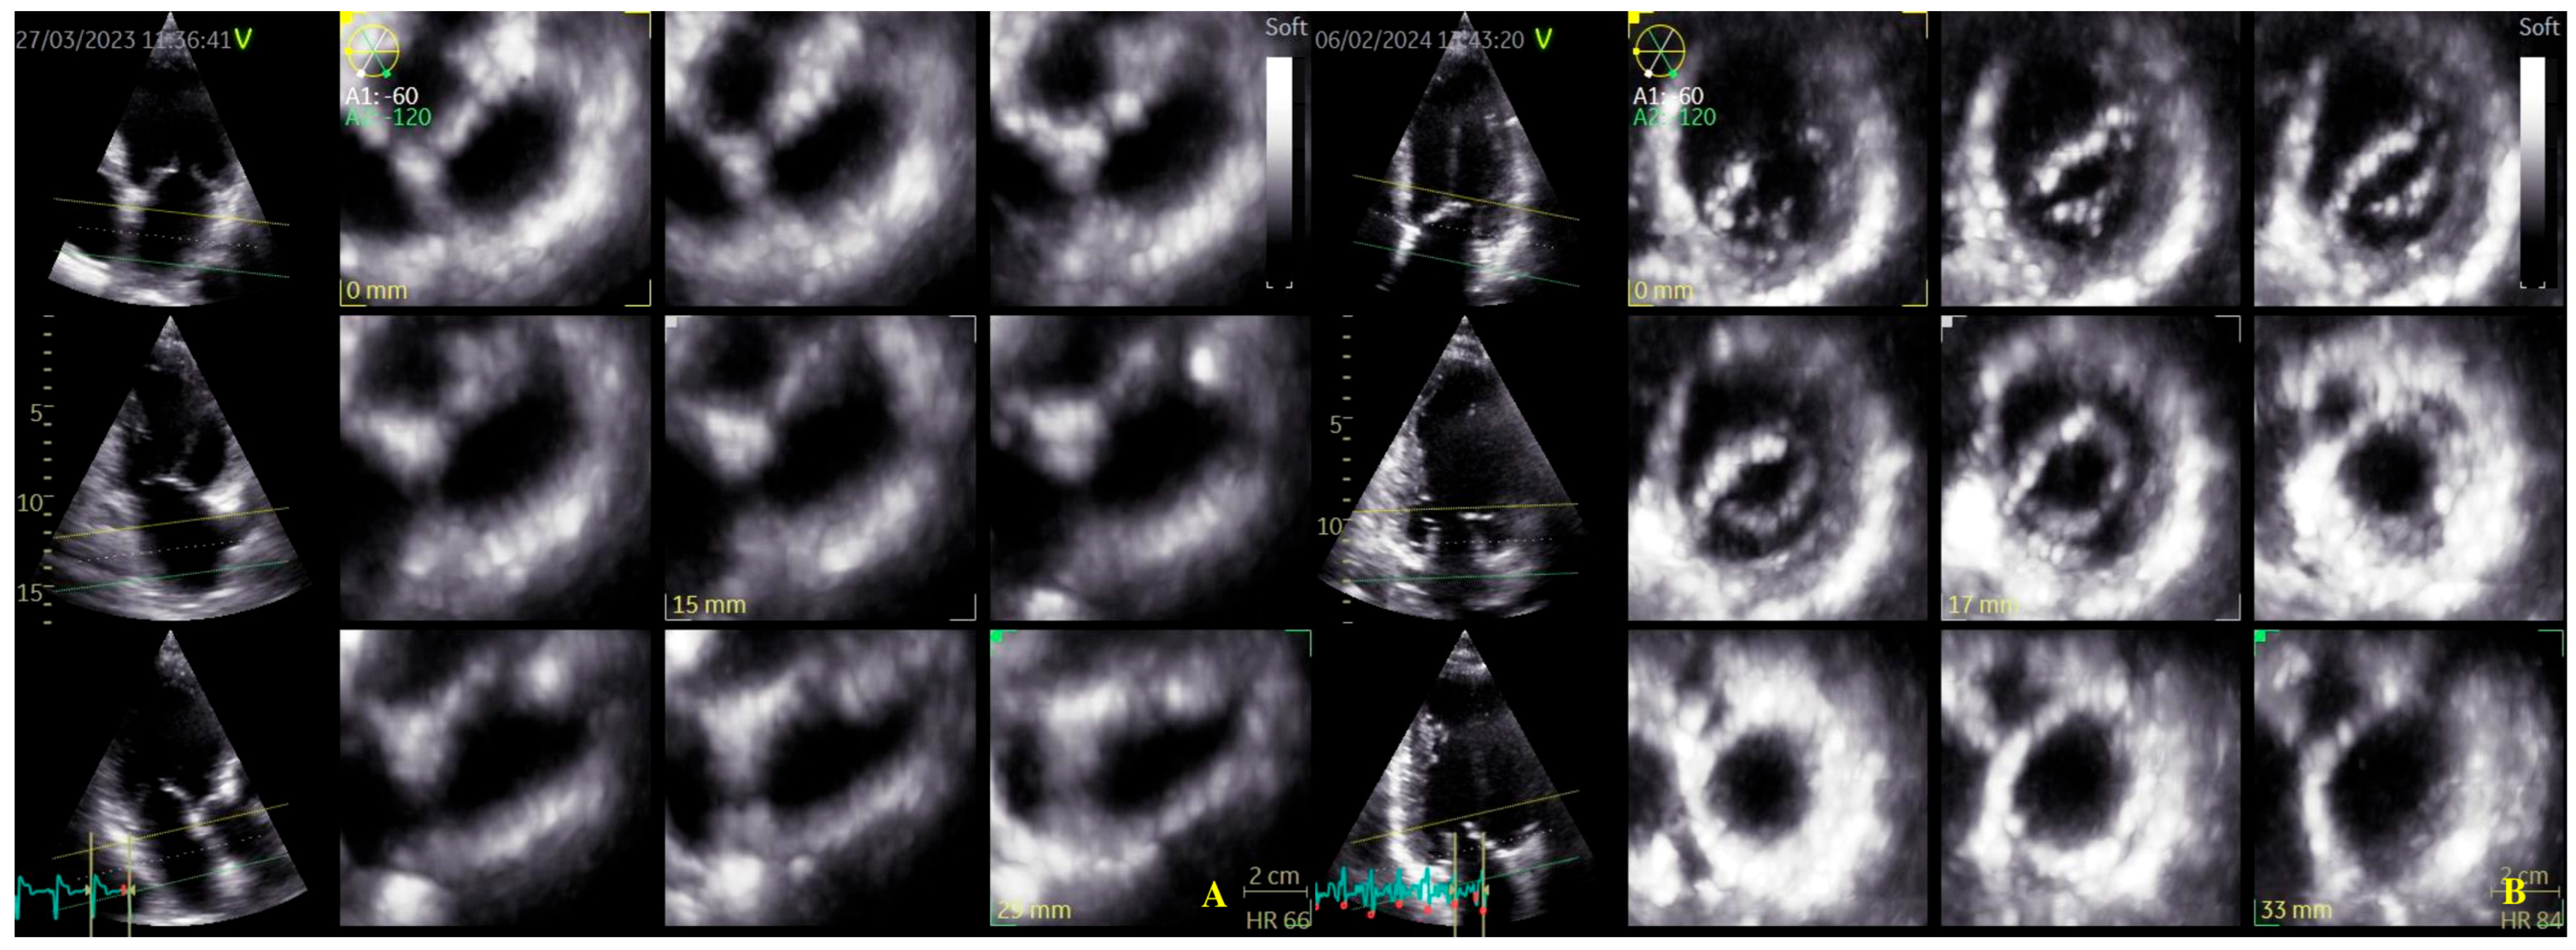

Four-dimensional echocardiograms were acquired using live 4D imaging in AF patients and electrocardiographically (ECG)-gated 4DE acquisition for SR patients. In live 4D imaging, a volumetric data set of a relatively narrow pyramidal sector is acquired and displayed in RT. In ECG, multiple-beat acquisition volumes are stitched together during four consecutive heart cycles during a single-breath hold. The minimum volume rate for LA 4DE strain measurements was 25 volumes per second (VPS) (Figure 1A); for MV 4DE measurements, it was 16 volumes per second (Figure 1B). Care had been taken regarding the volume rate because, as previously shown, a low temporal resolution might lead to an underestimation of strain magnitude [16,17,18].

Figure 1.

Four-dimensional transthoracic echocardiography (4D TTE) acquisition: (A) LA multi-slice acquisition; (B) MA multi-slice acquisition.